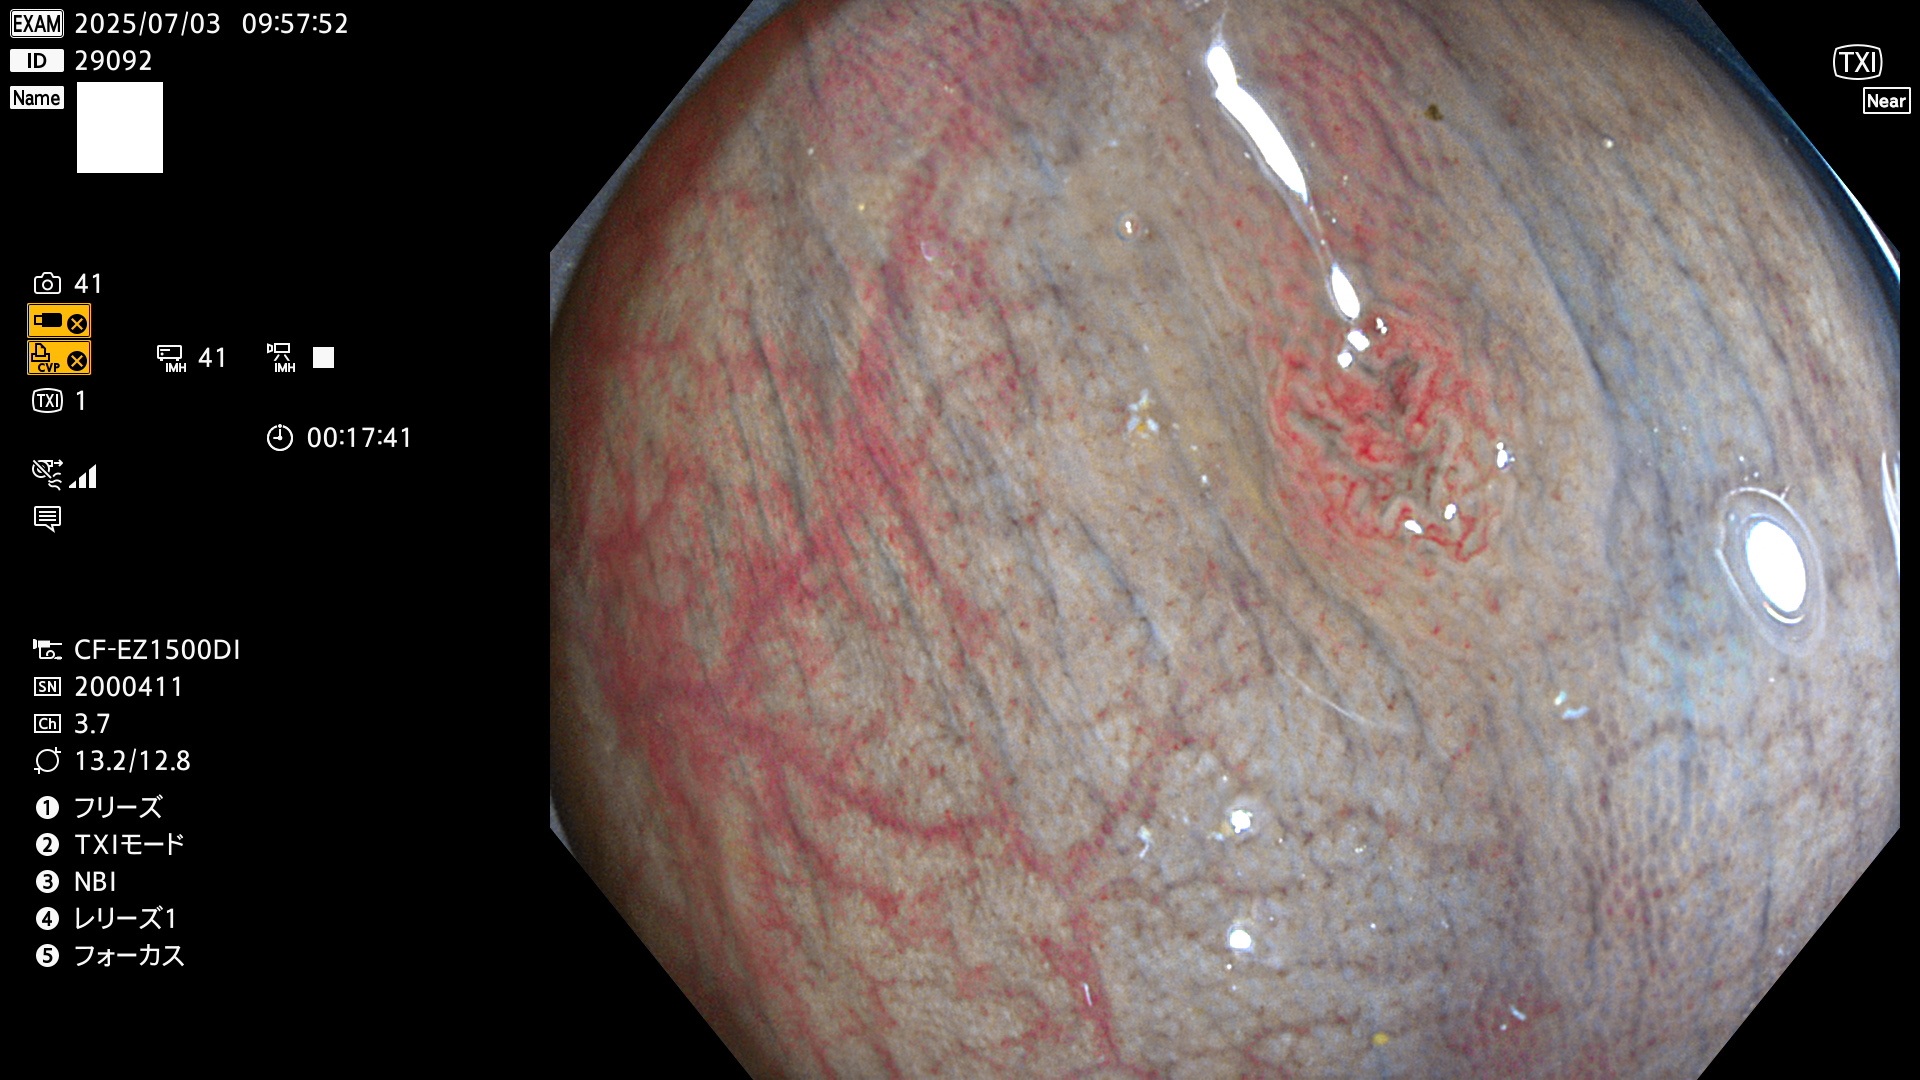

2025年7月3日〜7月6日の4日間(40件)8個 (Uc_ADR=8/40=20%)

びらん(炎症)と紛らわしいUc

完全に平坦な物をUb、陥凹している物をUcと呼びます。Ubは認識が困難で、Ucはびらん(炎症)と紛らわしいために見落とされやすく、「内視鏡後・大腸癌」の原因になります。